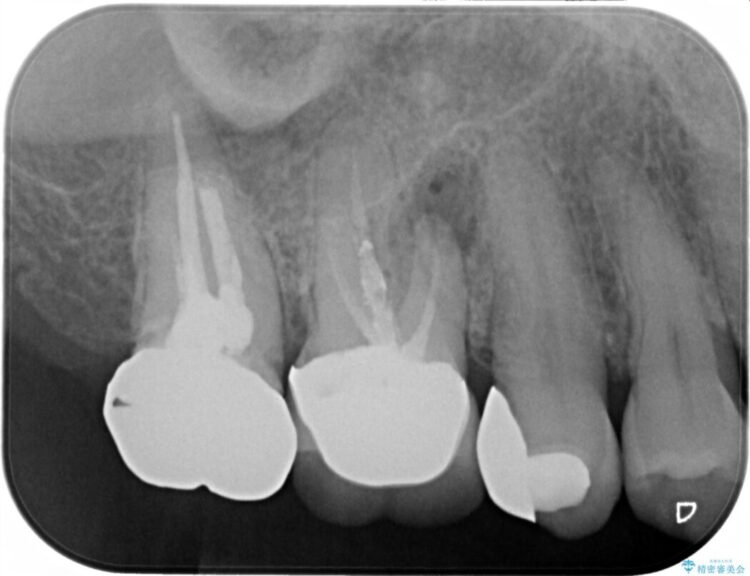

X線画像を診断すると、充填不良の根管の先に透過像が認められたため、再根管治療をご提案いたしました。